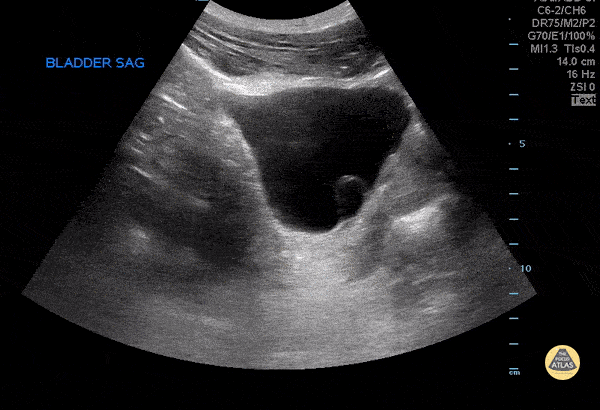

A 27 year old female with no significant past medical history, presented to the emergency department for dysuria. POCUS demonstrated a ureterocele seen projecting into the bladder. Mario Corro, MD, PGY-3 Staten Island University Hospital